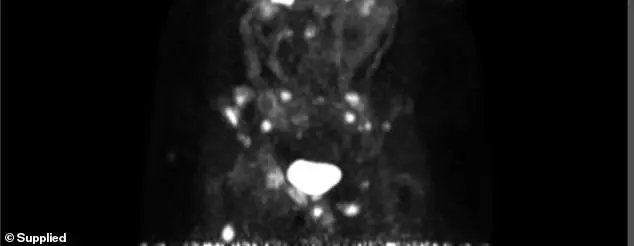

A year after Jess was in remission, scans revealed bone metastases. ‘My world just shattered -again,’ Jess said

Thankfully, the chemotherapy reduced all the cancer spots to a microscopic size.

Jess now undergoes regular scans to ensure the cancer spots do not increase – so far, results are promising.